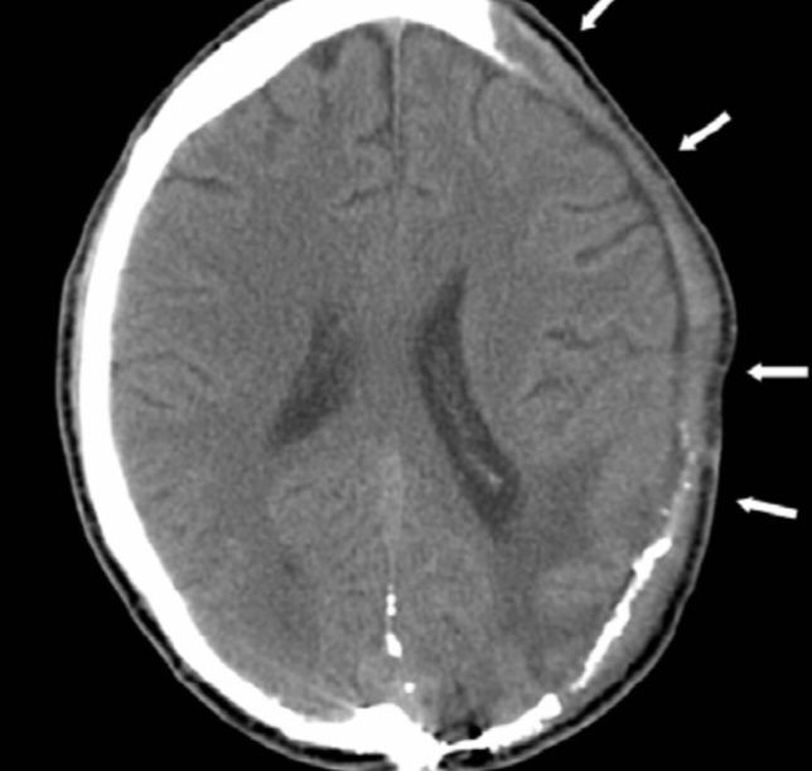

Craniectomy

Decompressive craniectomy is a neurosurgical procedure in which part of the skull is removed to allow a swelling brain room to expand without being squeezed. It is performed on victims of traumatic brain injury, stroke and other conditions associated with raised intracranial pressure.